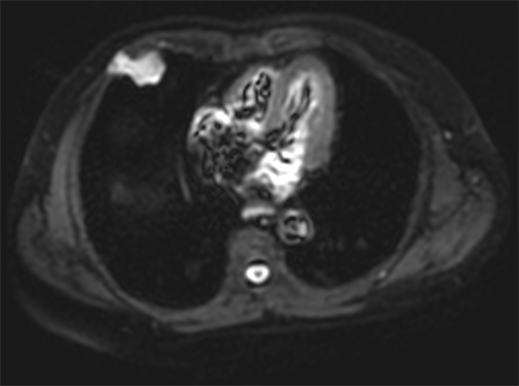

A 60-year-old Hispanic male presented to his primary care physician office with an asymptomatic, but palpable right anterior chest wall mass. The patient has no significant past medical history except for a clavicular fracture sustained during soccer. Physical examination revealed an asymptomatic 4 cm soft tissue palpable mass of the right anterior chest wall. The skin was intact, no erosive markings were present. The patient’s laboratory work up was unremarkable. Radiology work up included CT chest, MRI of the chest and PET/CT. His CT chest axial series on bone windows demonstrated a 2.8 × 3.8 × 2.9 cm pleural based soft tissue mass eroding through the right anterior fifth rib (Figure 1). There was mild compression of the nearby lung parenchyma, however no pulmonary lesions were identified. Further characterization of the mass by MRI contrast enhanced images of the chest revealed a well-circumscribed pleural based T1 hypo-intense avidly enhancing soft tissue mass in the right anterior chest wall involving the right anterior fifth rib and into the overlying sub-pectoral soft tissues (Figure 2). The mass also demonstrated restricted diffusion which is indicative of high cellularity (Figure 3 and Figure 4). PET/CT imaging revealed mild hypermetabolic activity of the mass with maximum SUV of 1.9 (Figure 5).

Figure 3. Diffusion weighted imaging (DWI) of the anterior chest wall mass shows hyperintense signal with corresponding hypointense signal on apparent diffusion imaging (ADC) shown in Figure 4, which indicates with the high cellularity of the tumor.